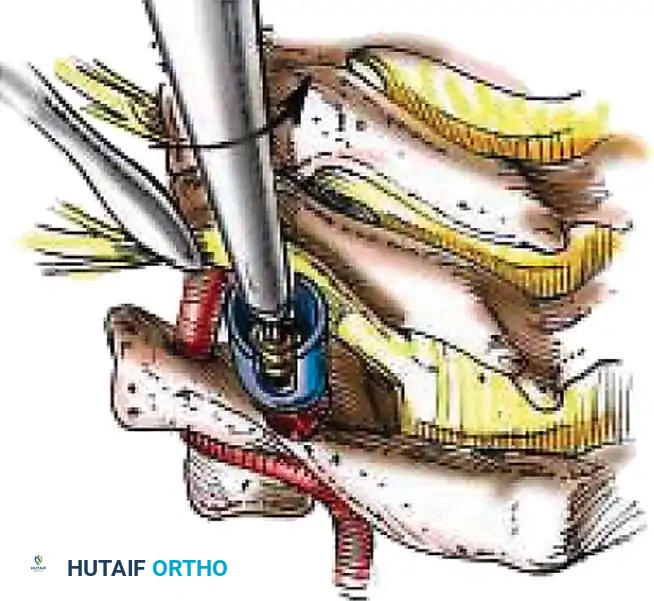

Posterior Cervical Fusion (PCF) and Instrumentation

Indications: Posterior tension band failure, irreducible facet dislocations requiring open reduction, or multi-level instability.

Positioning & Approach:

* The patient is carefully log-rolled prone onto a Jackson table. The head is secured in a Mayfield pin fixator.

* A midline posterior incision is made, utilizing the avascular ligamentum nuchae plane to expose the spinous processes, laminae, and lateral masses out to the medial border of the facet joints.

Surgical Steps:

1. Open Reduction: If a facet is dislocated, carefully lever the inferior articular process of the superior vertebra over the superior articular process of the inferior vertebra using a Penfield elevator.

2. Lateral Mass Screw Fixation:

* Utilize the Magerl or Roy-Camille trajectory.

* Magerl Technique: The entry point is 1 mm medial and 1 mm superior to the center of the lateral mass. The drill is angled 25 degrees laterally (to avoid the vertebral artery) and 15 degrees cephalad (to avoid the exiting nerve root).

3. Rod Contouring: Contour titanium or cobalt-chrome rods to match the patient's natural cervical lordosis and secure them to the screw heads with set screws.

4. Decortication and Fusion: Aggressively decorticate the lateral masses and facet joints with a high-speed burr. Pack the gutters with cancellous autograft (often harvested from the iliac crest) or high-quality allograft.

Fig 7. Posterior cervical lateral mass screw and rod construct, providing excellent biomechanical stability for posterior tension band failures.